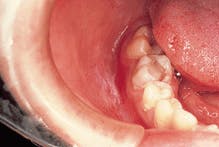

Case 5

Eruption Cyst

2. Identify the age group associated with the eruption cyst.

3. Identify the treatment of choice for the eruption cyst.

4. Identify the true statement concerning the eruption cyst.